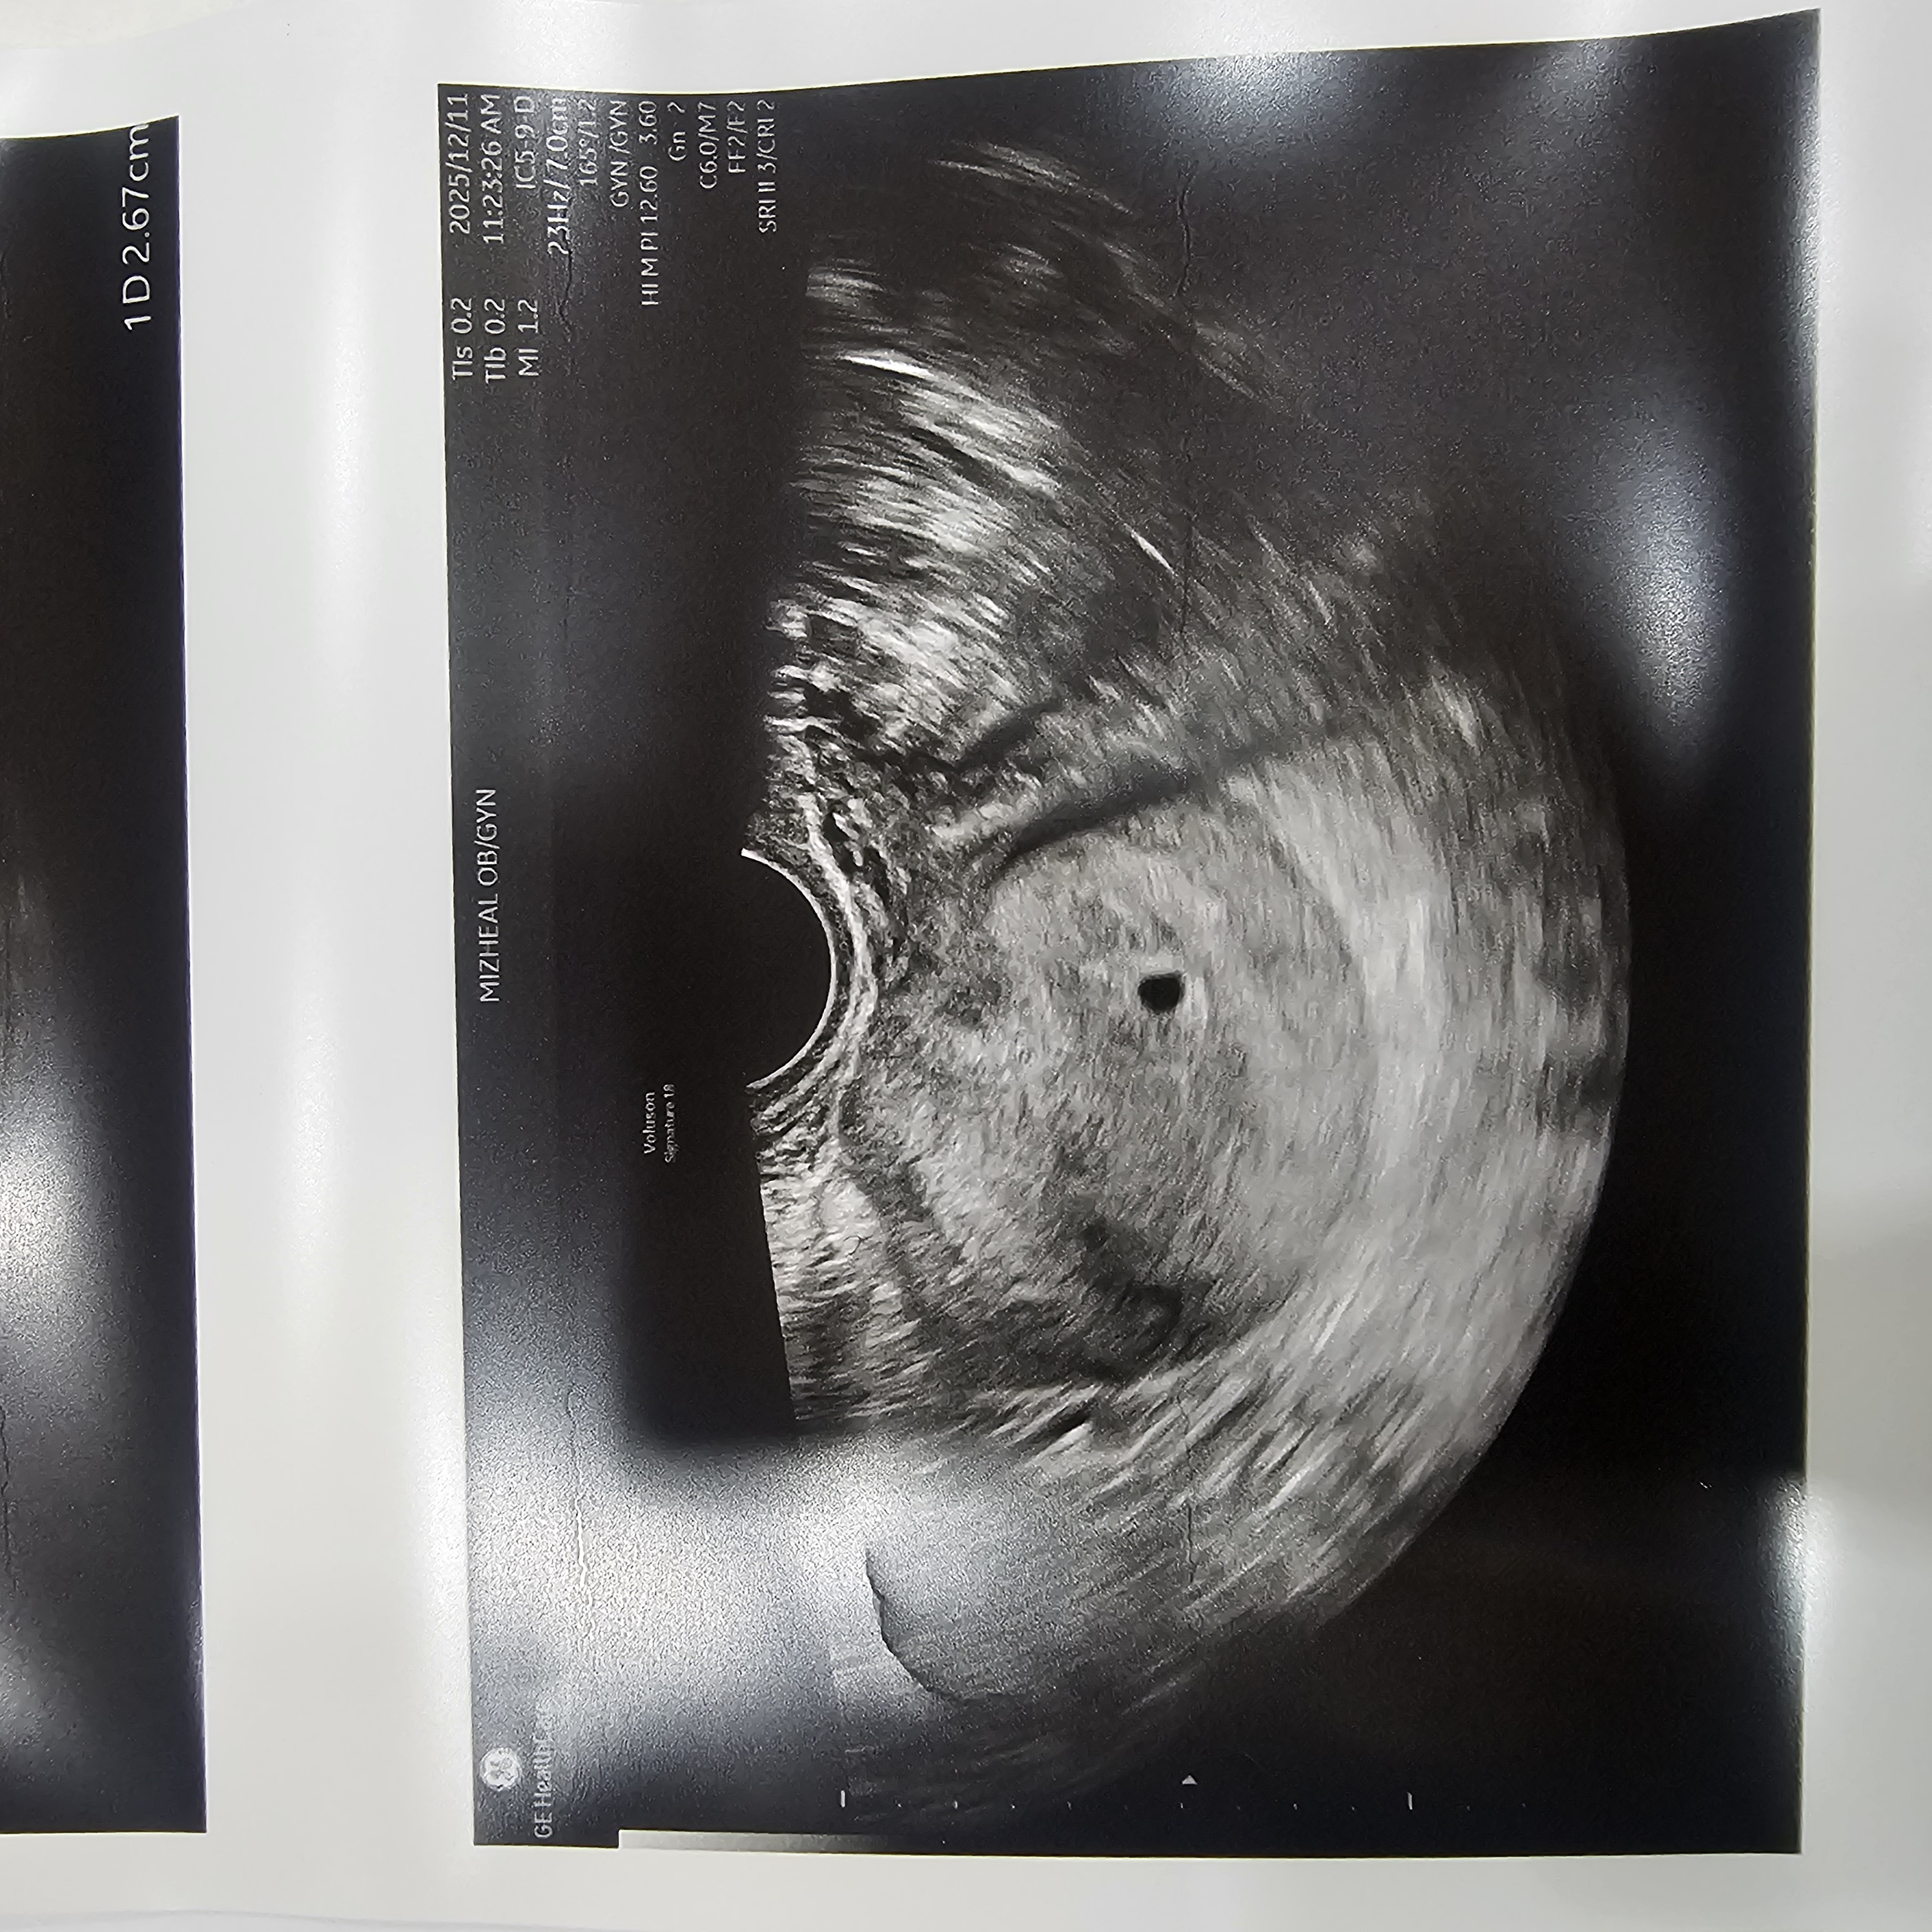

오늘 5주0일 임신확인 했습니다.

월요일 확답을 못받고 조마조마ㅜ 오늘 병원가서 초음파 보고 임신확인서 받아왔습니다ㅜ감동감동ㅜ